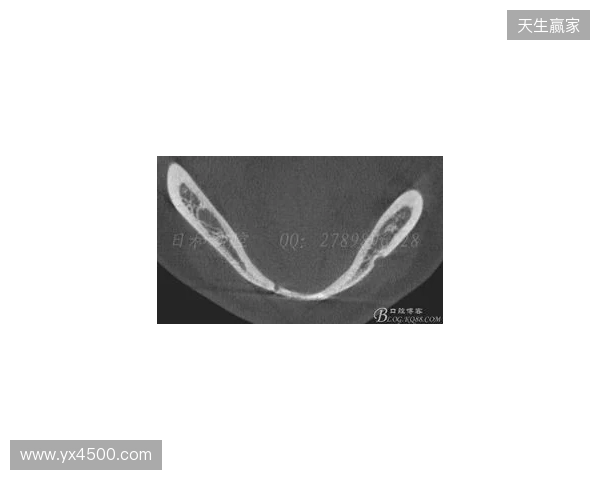

韦林顿确诊上唇部贯通伤;11、21牙半脱位;上颌前牙区牙槽骨骨折

根据医院的检查结果,韦林顿·席尔瓦的上唇部受伤程度较为严重,属于贯通伤,已经进行了清创缝合。这种类型的伤势不仅影响外观,还可能对球员的饮食和发声造成影响。更为严重的是,他的上颌前牙区还出现了骨折,意味着席尔瓦在恢复期间将面临长时间的治疗和康复过程。

球员的第11和第21牙出现了半脱位的情况,这可能会导致他在恢复后需要进行进一步的牙科治疗,甚至有可能影响到他今后的职业生涯。医生表示,虽然通过手术和治疗可以恢复,但心理层面的恢复同样重要。